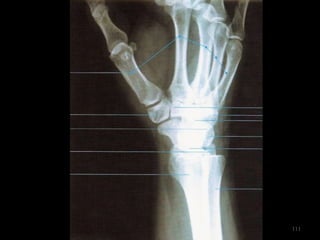

Incidência punho desvio (flexão) radial- PA de punho106

107